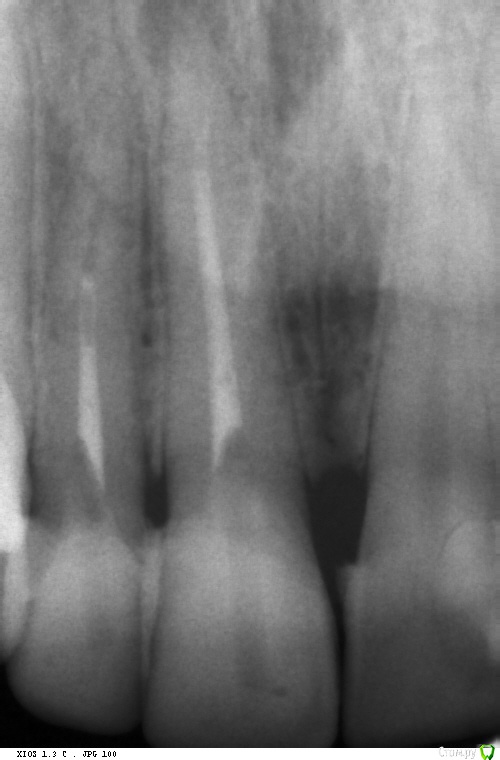

Anna84 Опубликовано 28 марта, 2017 Поделиться Опубликовано 28 марта, 2017 (изменено) Здравствуйте ! Проблема следующая: для лечения кистогранулемы необходимо зайти в каналы. В зубе стоит штифт стекловолокно. Была уже 2 раза у врача, она не может этот штифт рассверлить, чтобы добраться до канала. Первый раз заложила лекарство, через 3 дня я пришла и опять ничего. Заложила лекарство второй раз. Лекарство - для размягчения штифта. Врач говорит - если и в третий раз не получится, то она отправит меня к врачу, который лечит через микроскоп. Говорит, что боится делать отверстие в зубе больше, т.к. моя реставрация может не выдержать и зуб развалится. Посоветуйте, пожалуйста, как быть. Правильно ли все делает врач, или мне нужно найти другого ? Лечение зуба под микроскопом мне выйдет очень дорого, я все равно собиралась ставить коронку на этот зуб или менять реставрацию. Может, стОит сказать доктору, чтобы делала отверстие какое нужно и не смотрела на то что зуб может развалиться ? Или врач просто не очень грамотна ? Зуб - единица впереди. Заранее благодарю за помощь. Изменено 28 марта, 2017 пользователем Anna84 Ссылка на комментарий

АнтонТЛТ Опубликовано 28 марта, 2017 Поделиться Опубликовано 28 марта, 2017 Штифт надо аккуратно извлечь, максимально сохранив ткани зуба. Если просто просверлить, то зуб может в конечном итоге лопнуть пополам. Вывод: лучше поднакопить и сделать хорошо, чем сделать кое-как с отсроченной потерей зуба. 2 Ссылка на комментарий

DmitrySH Опубликовано 28 марта, 2017 Поделиться Опубликовано 28 марта, 2017 я это поняла....я имею в виду, стОит ли говорить доктору, чтоб сверлил как хочет но пусть высверливает штифт, даже если сейчас это грозит потерей реставрации ? В таком случае может произойти перфорация корня и это действительно будет проблемой. Потребуется удаление зуба. Ведь лечение с микроскопом мне обойдется дорого, смысл в нем чтобы сохранить ту реставрацию, которую я все равно буду переделывать ? Смысл в сохранении корня зуба, а не реставрации Или в микроскопе все равно будет необходимость, т.к. штифт этот даже если просверлить дыру на ползуба все равно не пройти ? Сложно предугадать 1 Ссылка на комментарий